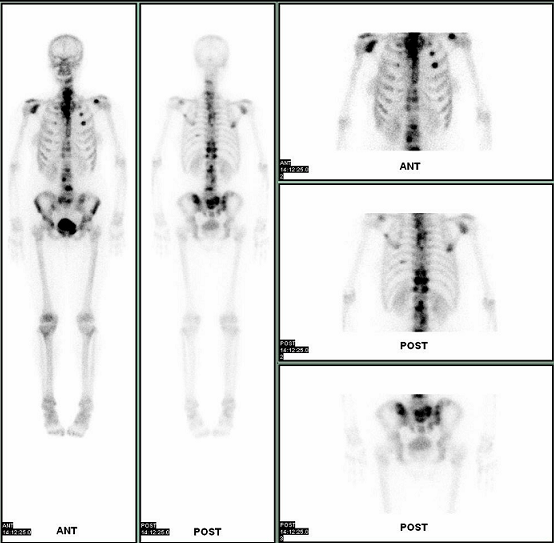

尽管检查骨骼病变的方法很多,如X线、CT、MRI等,但都不能一次完成全身所有骨骼的检查。只有ECT全身骨显像能够一次扫查完成全身骨的检查并且灵敏度高。只要骨骼的代谢、血流等发生改变,全身骨显像就能发现异常。尽管锝标记的亚甲基二磷酸盐骨显像一般没有特异性,但不同疾病的骨影像有一定的特殊征象,可提示特异性诊断。

全身骨显像广泛用于临床30多年来,成为临床检查骨病变尤其是恶性肿瘤骨转移全身检查及疗效随访的最有效、最简便、最快捷、最常用的手段。是肿瘤病人治疗前后常规检查的项目之一,以排除骨转移的存在。对于肿瘤骨转移的发现可以比普通X线早3-6个月。恶性肿瘤如肺癌、乳腺癌、鼻咽癌、前列腺癌等发生骨转移几率较高(可达60%~70%),多数的最初症状为持续加重的骨痛,以腰背部和腿疼多见,易误诊为其他疾病。部分患者(约20%)发生骨转移时无任何症状,部分肿瘤患者不知道原发肿瘤的存在,因骨痛来医院就医,骨显像结果提示骨转移,进而进一步检查发现了原发肿瘤的存在。因此无明显原因的骨痛,全身骨显像是非常必要的检查之一。